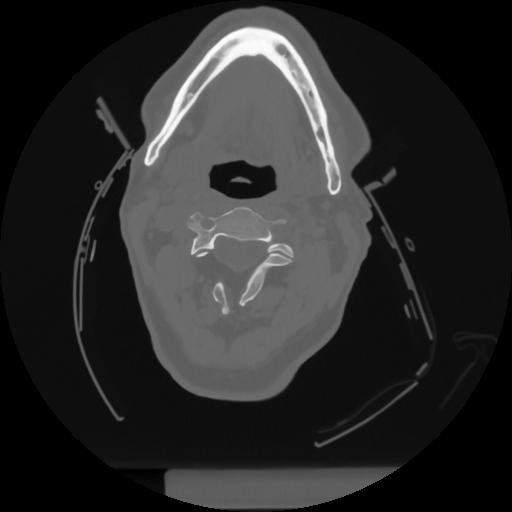

12 P.BLANDAS,,Vol,0.5,P.BLANDAS,,